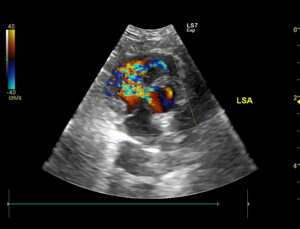

1 yr BSH, 4/6 murmur. Scan- normal LV, some RVH- annular FW and apically creating a DCRV effect (likely the source of the murmur). CFD- alias. in the RV extending apically. Unable to get good view of potential VSD. RSA- CWD produced a 5.4m/s velocity- poor angle for DCRV but good for a VSD. Slightly obliqued LSA may show VSD but may be the result of some color bleeding(hard to repeat). LPSLA aorta to Ruar/RA may show VSD near the last of the clip b/w LV and AO into RV? Suspect a restrictive VSD based on exam and echo. Recheck with better sedation scheduled. Thoughts? Thanks!!